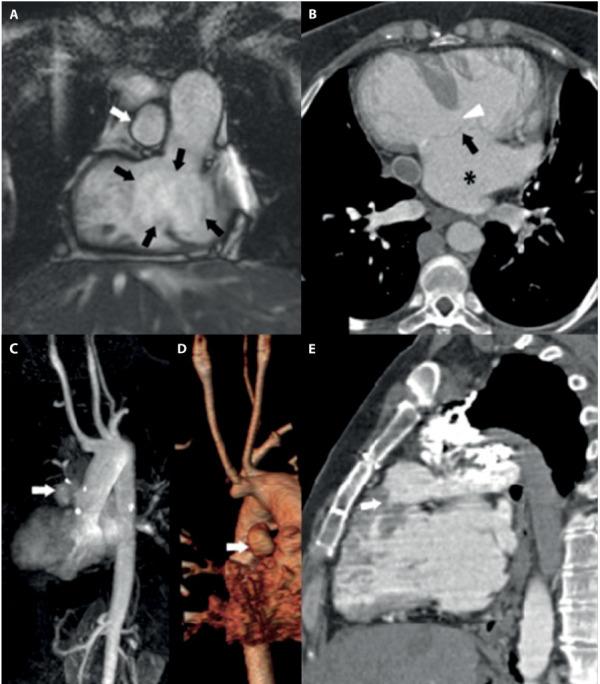

多模态影像学评估罕见且复杂的单心室生理学病例;心脏磁共振的重要作用。

Multi-modality Imaging Evaluation of a Rare and Complex Case of Single Ventricle Physiology; the important role of Cardiac MR.

Congenital heart diseases (CHD) represent a major clinical and diagnostic challenge for correct abnormality identification and subsequent successful therapy; even more challenging is following-up patient health after multiple post-interventional corrections often required in complex cardio-vascular abnormalities. We describe a multi-modality imaging evaluation of a complex congenital cardio-vascular diseases, underlining the relevance of cardiac magnetic resonance to non invasively solve some issues related to postsurgical changes.

先天性心脏病(CHD)是正确识别异常并随后成功治疗的主要临床和诊断挑战;更具挑战性的是在复杂心血管异常通常需要多次介入矫正后,对患者健康进行随访。我们描述了一种复杂先天性心血管疾病的多模态成像评估,强调心脏磁共振在无创解决与手术后变化相关的一些问题方面的相关性。